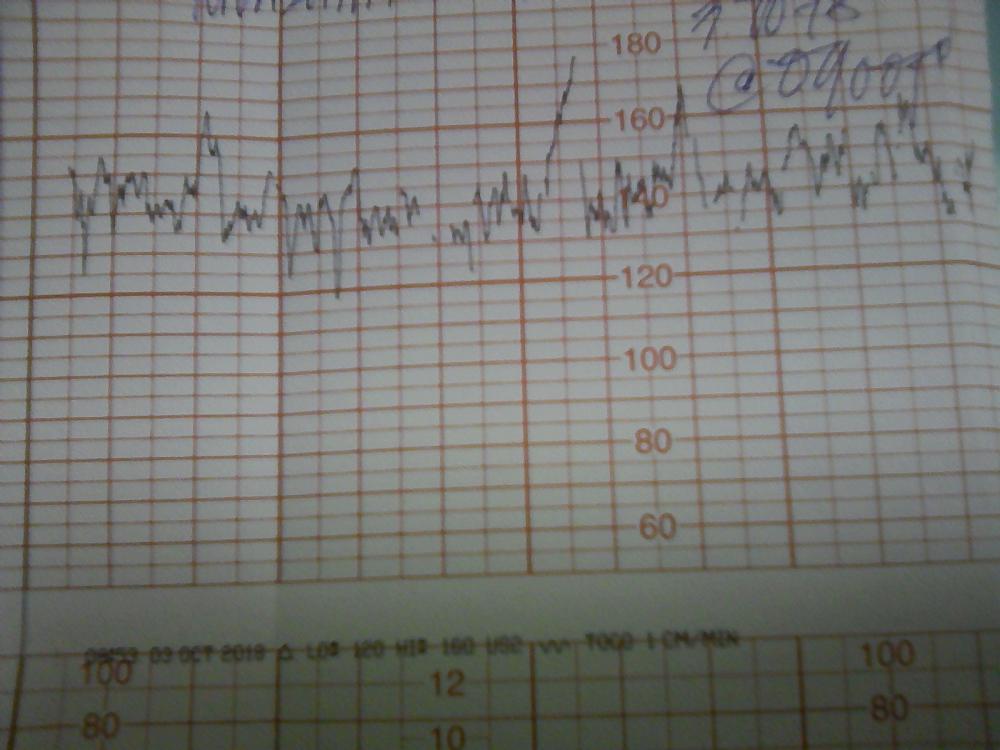

شوفو التخطيط فيه طلق أو لا والصور السوداء الباقي شنهي عنق الرحم أو الجنين مافهمت شيء لي ثلاث ايام بالتاسع وشكرا

شوفو التخطيط فيه طلق أو لا والصور السوداء الباقي شنهي عنق الرحم أو الجنين مافهمت شيء لي ثلاث ايام بالتاسع وشكرا

شوفو التخطيط فيه طلق أو لا والصور السوداء الباقي شنهي عنق الرحم أو الجنين مافهمت شيء لي ثلاث ايام بالتاسع وشكرا

شوفو التخطيط فيه طلق أو لا والصور السوداء الباقي شنهي عنق الرحم أو الجنين مافهمت شيء لي ثلاث ايام بالتاسع وشكرا